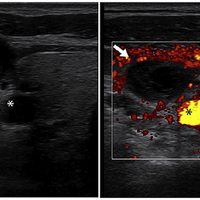

病歴 ・42歳男性 ・失神と頭痛のためER受診 ・BP90/60mmHg、他バイタルサインに異常なし ・ERでも強直間代性痙攣を発症し、自然に停止した 次の一手をどうしましょうか。 痙攣の原因検索として血液検査、心電図検査なんかを行いつつ、CTでしょうか? ・POCUSによりvolume status把握も兼ねて内頸静脈が検査された ◦右内頸…